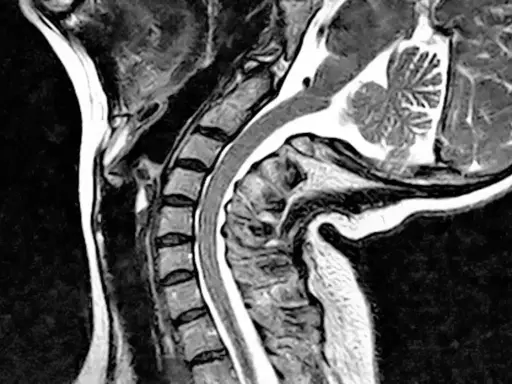

However, what are even less-readily diagnosed are craniocervical and atlantoaxial instabilities (CCI and AAI). These conditions are characterised by the joints in the cervical junction moving in ways they wouldn’t in someone without EDS. It means that often, blood flow to the head is restricted, and nerves in the neck are compressed or even damaged.

In the worst cases, any injury to a person’s neck or head can cause cerebrospinal fluid leaks from either the neck or head areas. Crucially, CCI and AAI can also be so severe that a person’s brain and skull begin to sink onto their cervical junction – which can be life-threatening.

Yet on the NHS, these conditions are not recognised in the context of EDS and HSD. They cannot readily be diagnosed due to the need for an upright MRI scanner. And if they even are, there are no treatment options available.